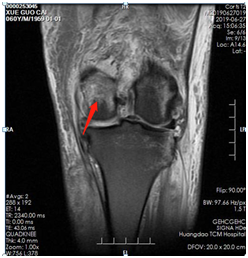

薛大叔左膝外侧有(以腓骨小头为中心)约10cmX15cm皮肤挫伤,其中间约5cmX8cm皮肤色紫,血运差;膝关节内上侧有约6cmX25cm皮肤挫伤,血运不满意 。医生为其进行了详细检查,确诊为左股骨内后髁骨折(Hoffa骨折)、左腓骨小头骨折、左膝内侧半月板损伤、左下肢挫裂伤 。

术前磁共振片